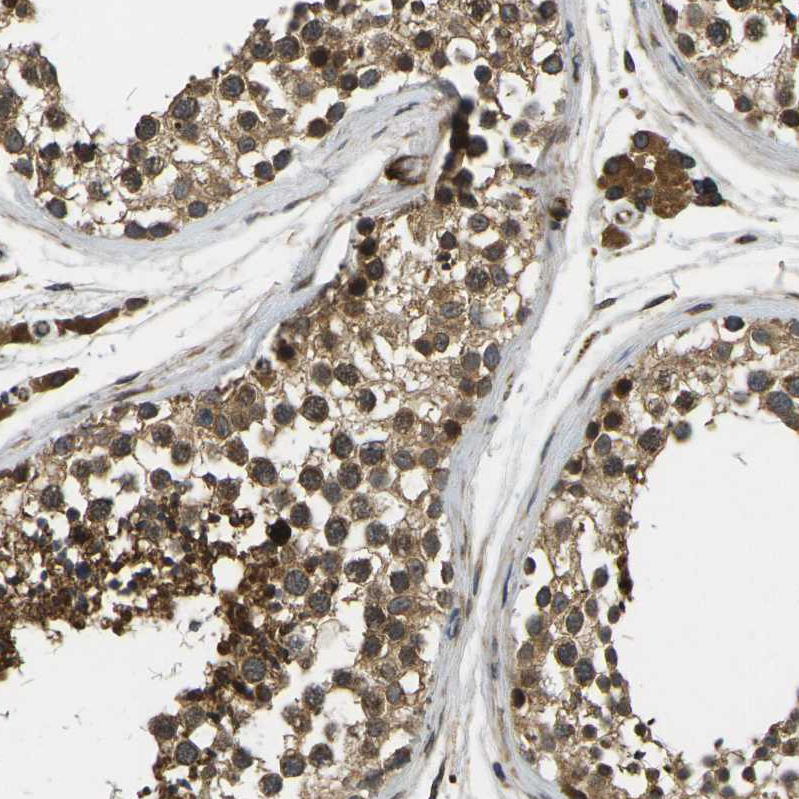

Immunohistochemical staining of human testis shows strong cytoplasmic membranous positivity in cells in seminiferous ducts and leydig cells.